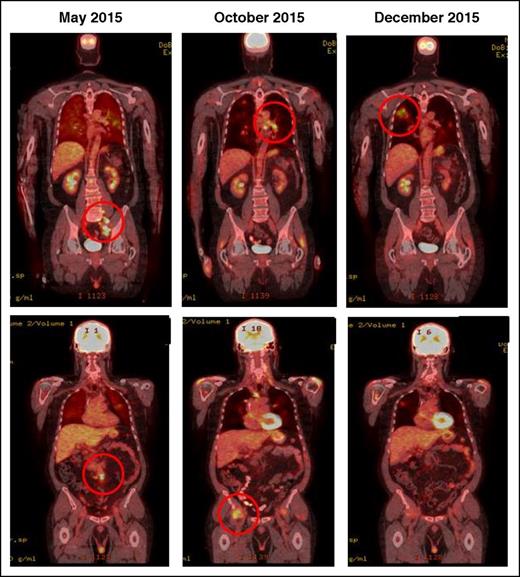

2. Appearance of new lesions or growth of one or more existing lesion(s) ≥50% at any time during treatment; occurring in the context of lack of overall progression (<50% increase) of overall tumor burden, as measured by SPD of up to 6 lesions at any time during the treatment [IR(2)] (Figure 4).

IR(2): CT demonstrating pseudo-progression in a patient on nivolumab for Hodgkin lymphoma. May 2015, pretreatment, October and December 2015 shows transient flares in different nodal groups without overall progression in the original target lesions.